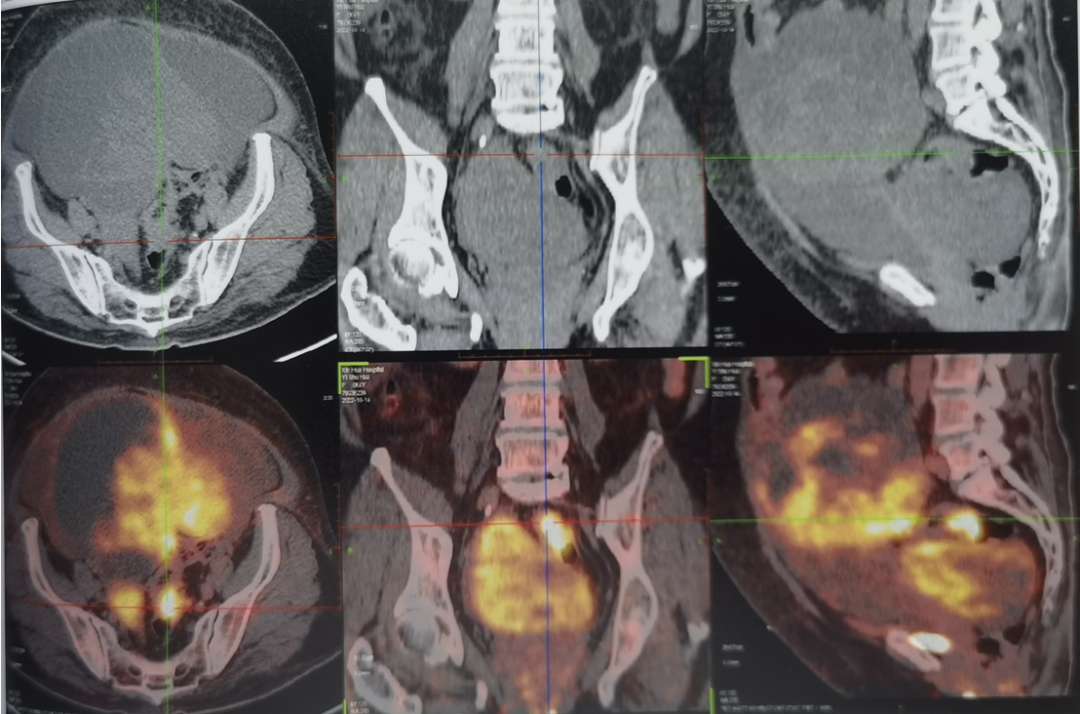

患者为64岁女性,5月余前体检查CT提示盆腔肿瘤,当时完善肠镜检查提示进镜18cm处见溃疡隆起病灶,病理:腺癌。外院经历FOLFIRI化疗、HIFU刀、腹腔灌注、子宫及卵巢动脉栓塞等治疗后,盆腔肿瘤及腹水缓解不明显,近5月体重下降约15kg。查PET-CT提示:1、盆腔左、右侧囊实性占位,大者13.8*21.3cm;2、肠系膜表面多发种植结节;3、腹腔大量腹水,左侧胸腔积液,肺不张。胸腔积液活检提示:细胞异型,腺癌转移可能。经MDT讨论患者拟行腹腔镜下乙状结肠切除+盆腔肿瘤切除术。

术前PET-CT:盆腔占位